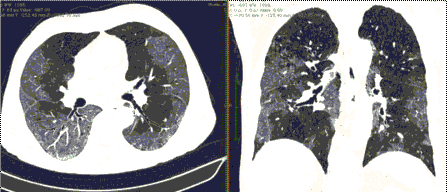

КТ имеет высокую чувствительность в выявлении изменений в легких, характерных для COVID-19. Применение КТ целесообразно для первичной оценки состояния ОГК у пациентов с тяжелыми прогрессирующими формами заболевания, а также для дифференциальной диагностики выявленных изменений и оценки динамики процесса. КТ позволяет выявить характерные изменения в легких у пациентов с COVID-19 еще до появления положительных лабораторных тестов на инфекцию с помощью МАНК. В то же время, КТ выявляет изменения легких у значительного числа пациентов с бессимптомной и легкой формами заболевания, которым не требуется госпитализация. Результаты КТ в этих случаях не влияют на тактику лечения и прогноз заболевания при наличии лабораторного подтверждения COVID-19. Поэтому массовое применение КТ для скрининга асимптомных и легких форм болезни не рекомендуется. При первичном обращении пациента с подозрением на COVID-19 рекомендуется назначать КТ только при наличии клинических и инструментальных признаков дыхательной недостаточности (SpO2 < 95%, ЧДД > 22).

3. Применение лучевых методов у пациентов с симптомами ОРВИ легкой степени тяжести и стабильном состоянии пациента, возможно только по конкретным клиническим показаниям, в том числе при наличии факторов риска, при условии достаточных технических и организационных возможностей. Методом выбора в этом случае является КТ легких по стандартному протоколу без внутривенного контрастирования или РГ при ограниченной доступности КТ. Использование УЗИ в этих случаях нецелесообразно. Применение КТ исследования в сроки ранее 3 - 5 дней с момента появления симптомов заболевания, а также при отсутствии клинических проявлений поражения бронхолегочной системы является нецелесообразным. Выполнение КТ целесообразно при наличии клинических и инструментальных признаков дыхательной недостаточности (SpO2 < 95%, ЧДД > 22), либо при дифференциальной диагностике с другим заболеванием.

4. Все выявляемые при лучевых исследованиях признаки, включая КТ-симптомы, не являются специфичными для какого-либо вида инфекции и не позволяют установить этиологический диагноз. Вне клинической (эпидемической) ситуации они не позволяют отнести выявленные изменения к пневмонии COVID-19 и дифференцировать их с другими пневмониями и невоспалительными заболеваниями. Данные лучевого исследования не заменяют результаты обследования на РНК SARS-CoV-2. Отсутствие изменений при КТ не исключают наличие COVID-19 и возможность развития пневмонии после проведения исследования.